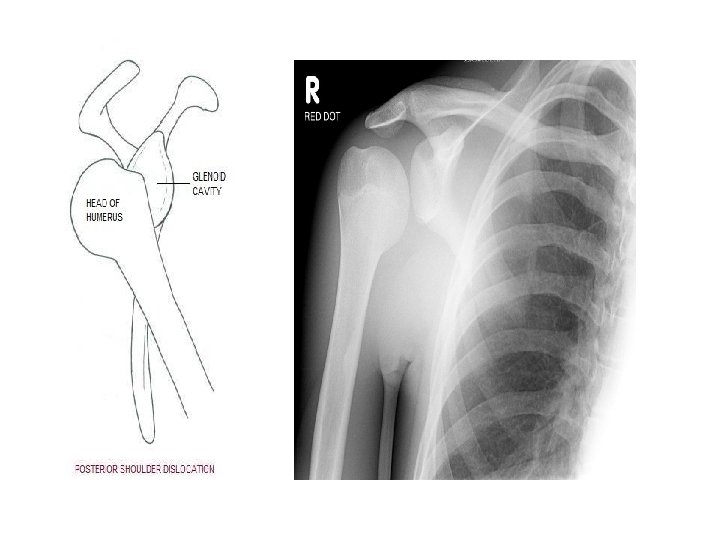

Applied Anatomy • Dislocation of shoulder joint -mostly occurs inferiorly. -axillary nerve injured due to close proximity. -clinically described as – anterior and posterior dislocation. -caused by excessive extension and lateral rotation of humerus. -presents as hollow in rounded contour of shoulder and prominent tip.